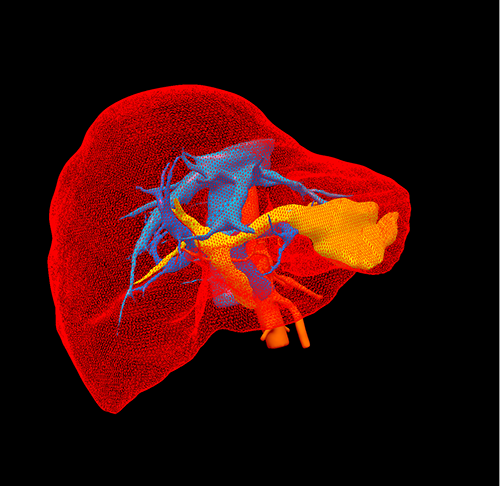

左肝胆管结石--腹腔镜左肝叶切除